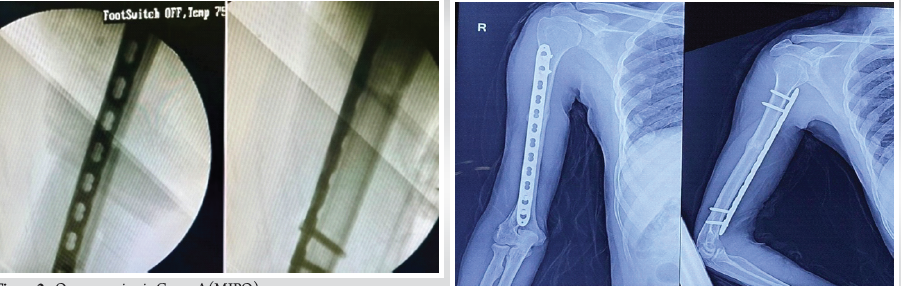

The mean time taken for union was 13.3 ± 3.1 weeks (95% confidence interval [CI]: 10.9–20) in Group A and 18.1 ± 4.7 weeks in Group B (95% CI: 12.1–24), which shows a significant statistical variation (P = 0.03, independent t-test). Both approaches helped in healing the bone, with Group A having a quicker union (Figs. 2A, 2B and 3) [1,2,4,7,15].

Fig. 2: Osseous union in Group A (MIPO (A)Intraoperative fluoroscopic orthogonal images demonstrating acceptable length and alignment of the fracture, with a narrow locking compression plate spanning the anterior cortex of the right humerus.

(B) The fracture was observed to have healed at 11 weeks post-surgery (indicated by the label ‘early callus’), with the 4 cortices touching on both AP and lateral images. The orientation is indicated by ‘R’ (right).